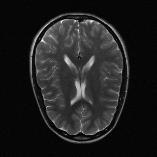

Recently, deep neural networks have greatly advanced undersampled Magnetic Resonance Image (MRI) reconstruction, wherein most studies follow the one-anatomy-one-network fashion, i.e., each expert network is trained and evaluated for a specific anatomy. Apart from inefficiency in training multiple independent models, such convention ignores the shared de-aliasing knowledge across various anatomies which can benefit each other. To explore the shared knowledge, one naive way is to combine all the data from various anatomies to train an all-round network. Unfortunately, despite the existence of the shared de-aliasing knowledge, we reveal that the exclusive knowledge across different anatomies can deteriorate specific reconstruction targets, yielding overall performance degradation. Observing this, in this study, we present a novel deep MRI reconstruction framework with both anatomy-shared and anatomy-specific parameterized learners, aiming to "seek common ground while reserving differences" across different anatomies.Particularly, the primary anatomy-shared learners are exposed to different anatomies to model flourishing shared knowledge, while the efficient anatomy-specific learners are trained with their target anatomy for exclusive knowledge. Four different implementations of anatomy-specific learners are presented and explored on the top of our framework in two MRI reconstruction networks. Comprehensive experiments on brain, knee and cardiac MRI datasets demonstrate that three of these learners are able to enhance reconstruction performance via multiple anatomy collaborative learning.

翻译:最近,深心神经网络大大推进了未经充分取样的磁共振成像(MRI)重建,其中大多数研究都遵循单一解剖一个网络的方式,即每个专家网络都经过特定解剖学的培训和评价。除了在培训多种独立模型方面效率低下之外,这种公约忽视了不同解剖学中共享的、可相互受益的解析知识。为了探索共享知识,一种天真的方法是将各解剖学家的所有数据结合起来,以训练一个全方位网络。不幸的是,尽管存在共享的解析知识,但我们发现,不同解剖学的独家知识可以恶化具体的重建目标,导致总体性能退化。在这项研究中,我们提出了一个新型的深度解剖重建框架,既有解剖学共享知识,又具有具体的解剖学参数,目的是“寻找共同的土壤,同时保留不同解剖学家之间的差异。此外,主要的解剖学学习者将接触不同的解剖学数据,通过多种解剖学重建的模型,并用不同的解剖学研究者将数据展示出一个全方位基础。